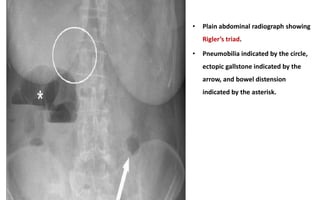

• The characteristic radiological sign of gallstone ileus on radiographs of the

abdomen is Rigler’s triad, comprising:

• Small bowel obstruction,

• Pneumobilia and

• Atypical mineral shadow (due to the stone outside the gallbladder)

• The presence of two of these radiological signs has been considered

pathognomic of gallstone ileus and is encountered in 40–50% of the

cases.

• Plain abdominal radiograph showing

Rigler’s triad.

• Pneumobilia indicated by the circle,

ectopic gallstone indicated by the

arrow, and bowel distension

indicated by the asterisk.